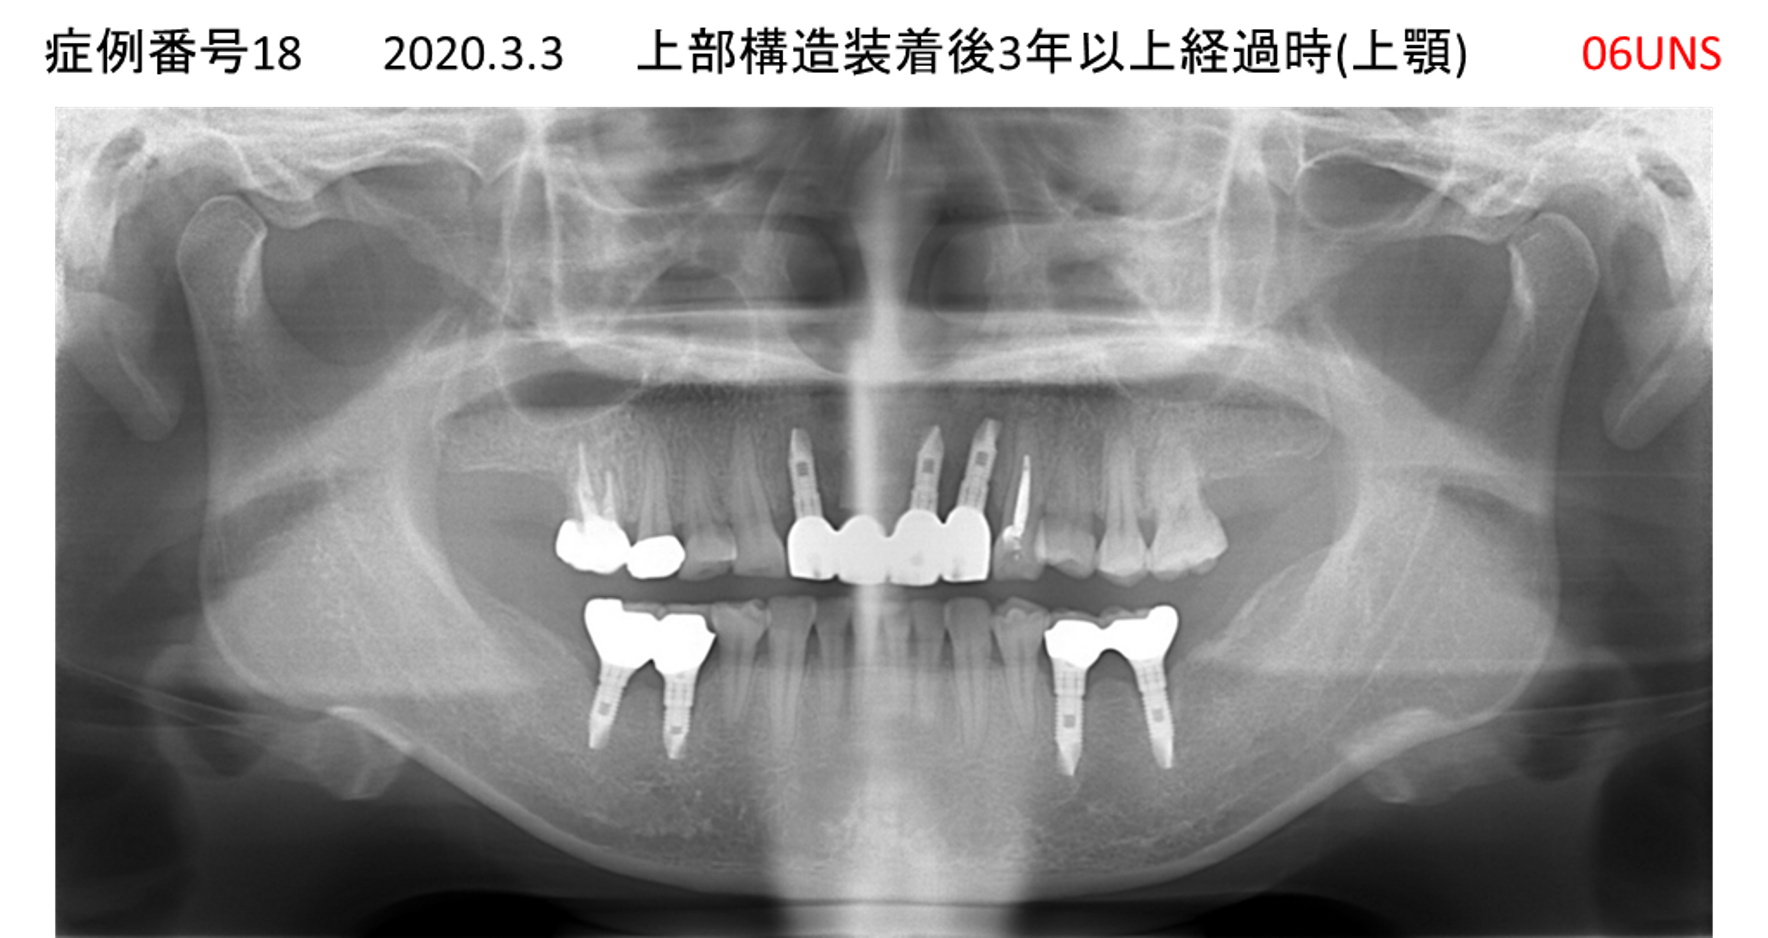

上の前歯が揺れてきてかめない患者様のインプラント症例

| 治療名称 |

インプラント |

| 治療費用 |

440万円+税 |

| 治療期間 |

6か月 |

| 患者さんの症状(主訴) |

上の前歯が揺れてきた。かめない |

| 治療内容 |

サイナスリフト、GBR、インプラント、即時荷重 |

| 治療結果 |

上の前歯の揺れが収まった。奥歯でしっかり噛める。 |

| 治療の注意点(リスク/副作用) |

インプラントが壊れたら再治療が必要 |